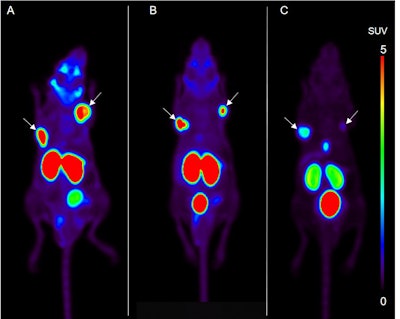

Soeda and colleagues used a mouse xenograft model for three groups of mice, which were divided by the amount of peptide injected into each subject. A decrease in the peptide concentration (or molar activity) level resulted in decreased uptake in the tumor and, to a greater degree, in the salivary glands.

Maximum intensity projections of F-18 PSMA-1007 PET images in xenografts of mice with high (A), medium (B), and low (C) concentrations of the agent. Tumors are indicated by arrows. Tumor uptake was lower in the low-concentration group, compared with the other two sets of mice. Images courtesy of Soeda et al and the Journal of Nuclear Medicine.The researchers found that the salivary glands showed a more sensitive decrease in uptake, compared with a reduced molar activity level of the radioligand solution than the tumors.

"This suggests that molar activity is an essential factor to define the optimal distribution for theranostic compounds," Soeda said in a statement released by the Society of Nuclear Medicine and Molecular Imaging. "There is a possibility of obtaining a therapeutic effect in the tumor, while minimizing the adverse effects in the salivary glands by setting an appropriate molar activity level in PSMA-targeted therapy."